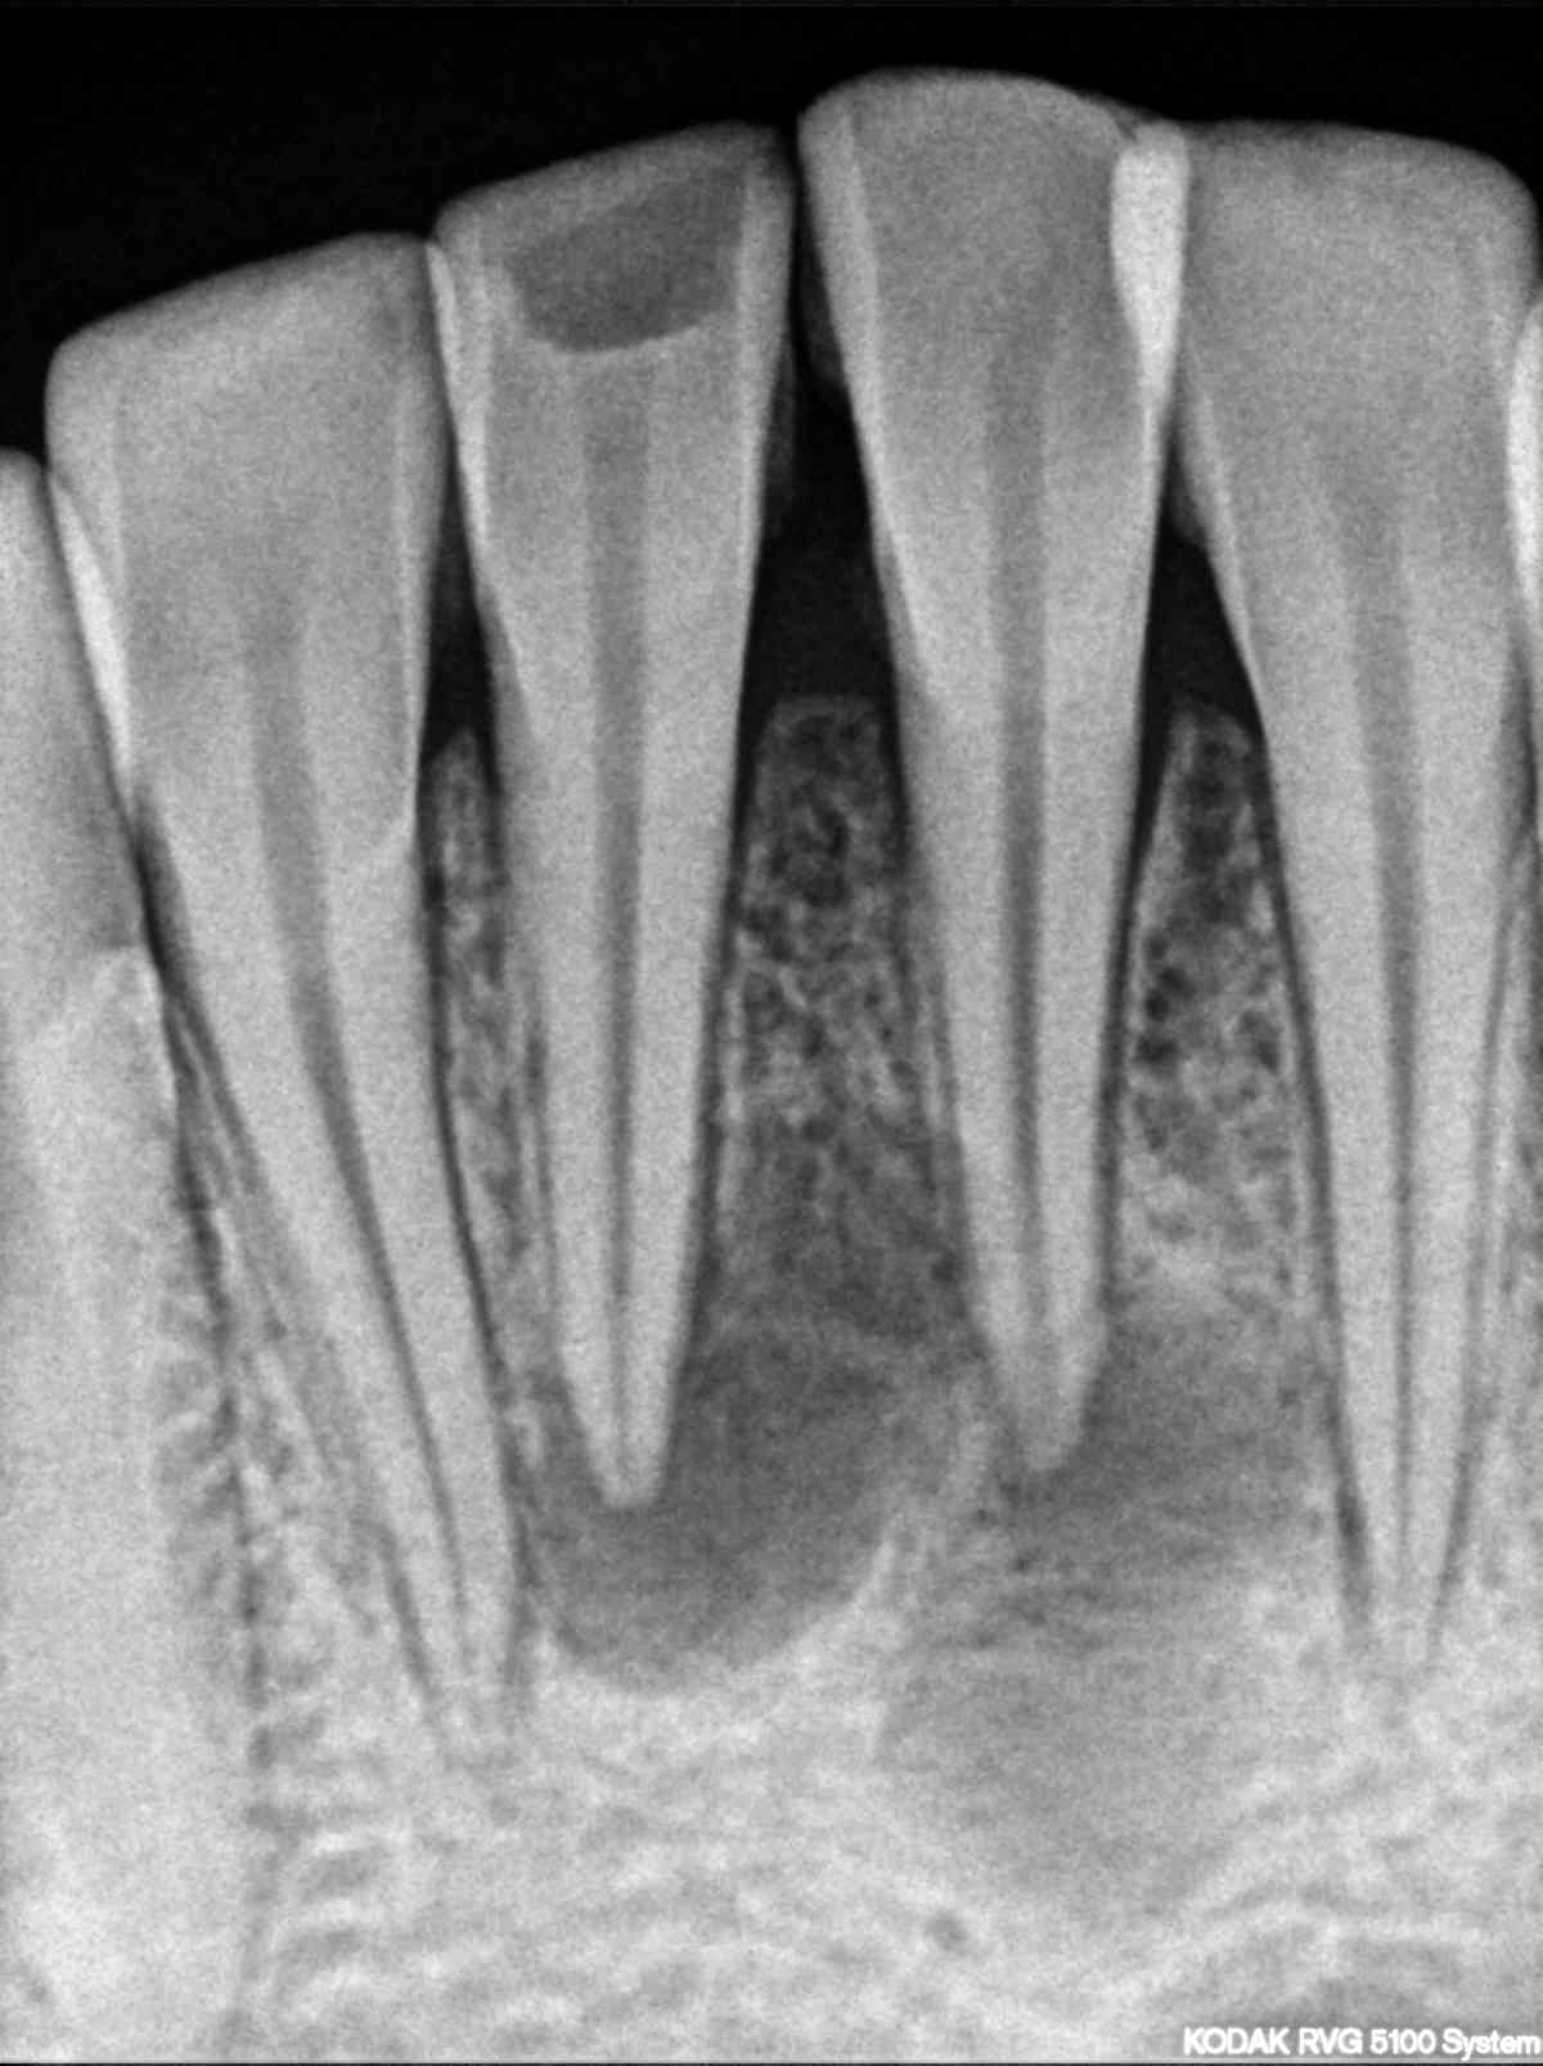

The patient had cutaneous opening of size 5mm × 6mm with purulent discharge in submental region. Patient had undergone three surgical excisions and multiple antibiotic regimens. Patient had a history of trauma due to fall six years back. A 30 number standard gutta-percha was used to trace the sinus tract and dental origin was confirmed radiographically. The tract led to in-between the root canal apices of both mandibular incisors. Treatment included non-surgical endodontic treatment with both mandibular central incisors and antibiotic coverage following bacterial culture of discharge. The pus culture showed Streptococcus anginosus which was found to be sensitive to penicillin. Patient was kept on 1-week course of oral amoxicillin-clavulanate along with root canal therapy.

The cutaneous sinus healed following root canal treatment and antibiotic coverage. On an 8-year follow-up skin of sub-mental region appeared normal and peri-apical healing with both mandibular central incisors was evident radiographically. Cutaneous lesions on face may be of dental origin. A cross referral between dentists, physicians, surgeons, and dermatologists should be considered in such cases.